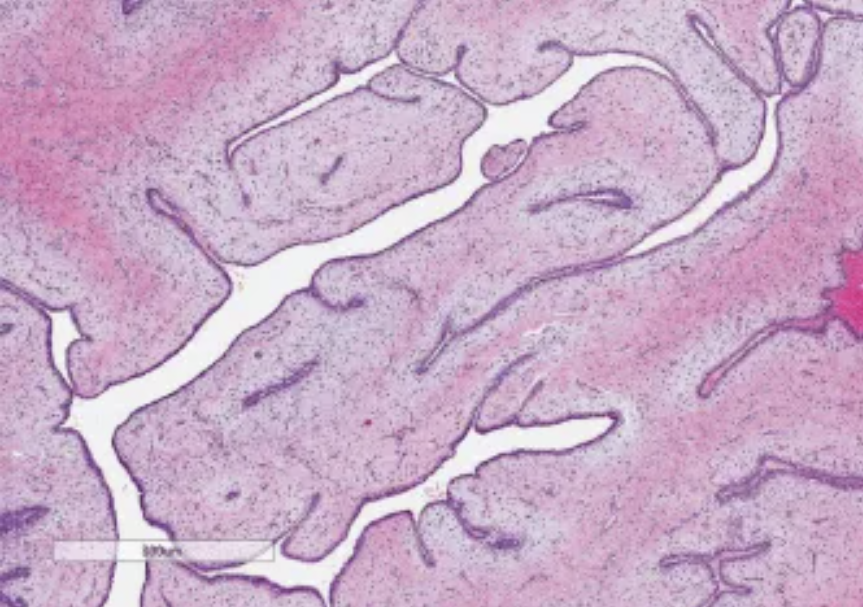

Phyllodes tumor

Biphasic tumor composed of spindled stromal cells and benign epithelial cells. Stromal cellularity is variable, and ranges from paucicellular to hypercellular. Prominent and exaggerated intracanalicular pattern with “leaf-like” projections into variably dilated lumina.

Shown is a benign phyllodes tumor, with a paucicellular stroma and stromal condensation under the epithelial-lining of the spaces.

Increased incidence in Li Fraumeni syndrome. Presents as a palpable, painless breast mass. Can have heterologous elements that are malignant.

Molecular: MED12 and RARA mutations in benign phyllodes tumors.

TERT promoter, ERBB4, TP53, EGFR, PIK3CA, and RB1 in borderline or malignant phyllodes tumors.